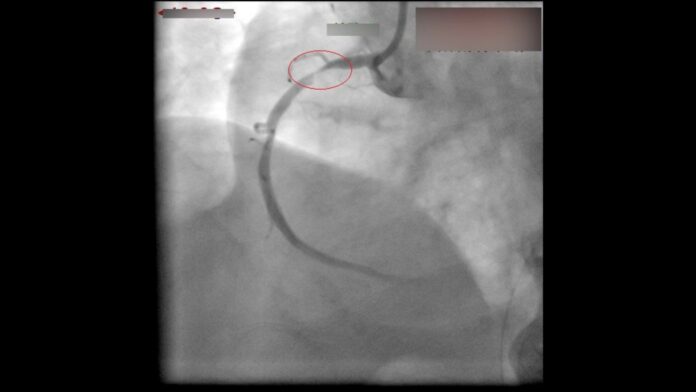

林婦被送往彰化醫院後,心導管室團隊早已嚴陣以待,搶分秒、拚時間。心導管室主任王彥翔表示,患者到院後立即進行心導管檢查,發現其心臟冠狀動脈竟有3處嚴重阻塞,導致心肌缺氧缺血,當機立斷立即為其植入3支支架,成功打通生命血路。